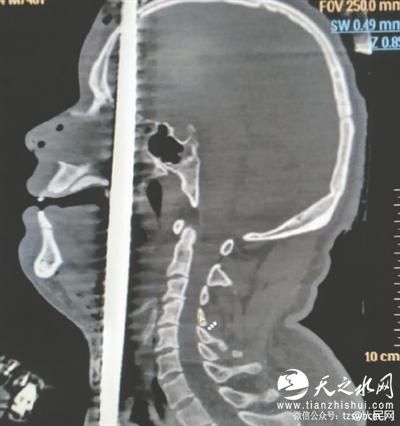

钢筋从右阴囊插入,头顶穿出 图据人民网

经检查发现,该男子意识清楚,鼻腔口腔有鲜血流出。钢筋从男子的右阴囊插入,途经泌尿系统,伤及腹部的肝脾,紧贴心脏和颈动脉贯穿而过。从咽喉直插入口腔,舌头,上颚经鼻腔,插入大脑,最后钢筋从头顶穿出。